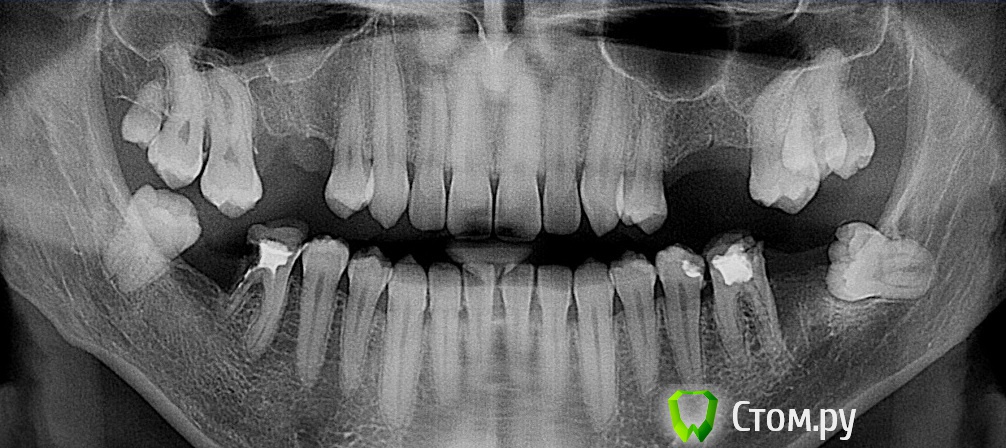

Шура Опубликовано 27 января, 2014 Поделиться Опубликовано 27 января, 2014 Пациент 15 лет. Удаление третьих моляров перед ортодонтическим лечением." Было у отца четыре сына, трое нормальных - а четвёртый ... " 3 Ссылка на комментарий

Чертков Александр Опубликовано 27 января, 2014 Поделиться Опубликовано 27 января, 2014 а четвёртый 6-7 корневых каналов...ммм...вот где эндодонтист "озолотиться" может! Ссылка на комментарий